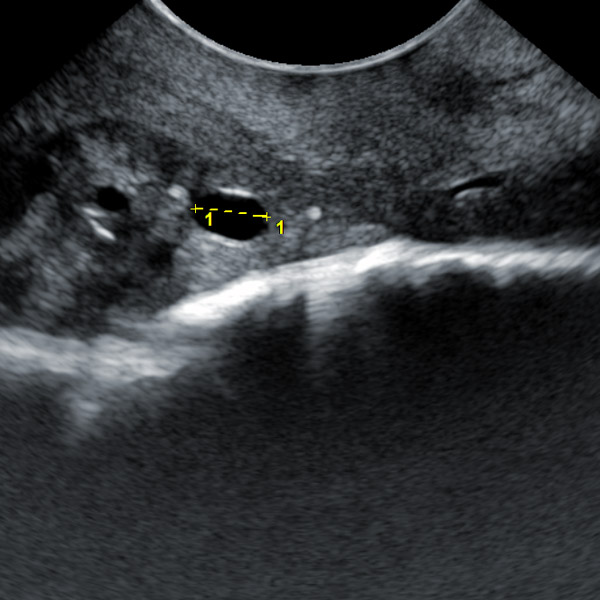

1. Animal OPU live egg collection probe:

1.1. Frequency 5.0-9.0MHz, non-porous, smooth surface, eagle-beak-shaped integrated micro-convex probe

1.2. Waterproof and dustproof probe

1.3. Number of array elements: 128 array elements

1.4. OPU gun length: 61.5cm (length can be extended according to needs); diameter: ≤2.5cm; weight: ≤700g Cable length: 200cm (standard), customizable length

1.8. Egg collection needle tube scale mark, used to control the depth of needle insertion

1.9. There is an egg collection needle guide line when collecting eggs, there is a scale ruler on the egg collection needle guide line, there is a center line on the egg collection needle guide line, and the image is enhanced when the egg collection needle is punctured

III. Product features of animal OPU live egg collection probe:

1. The eagle-beak-shaped integrated micro-convex live egg collection probe is a product carefully designed according to the clinical practice of the ranch. It has passed the clinical tests of technical experts in the field of animal reproduction for multiple OPU embryo transplantation. It is convenient for clinical operation and has a high egg collection efficiency.

4. There is an egg collection needle guide line when collecting eggs, a scale ruler on the egg collection needle guide line, a center line on the egg collection needle guide line, and an image enhancement design when the egg collection needle is punctured, which can greatly improve the direction sense and strength control of the needle during egg collection.

5. The diameter of the egg collection gun is very small and can be used for young cows of very young age.

6. High-frequency probe and high-quality Doppler color ultrasound images can observe the situation of follicles below 1mm.